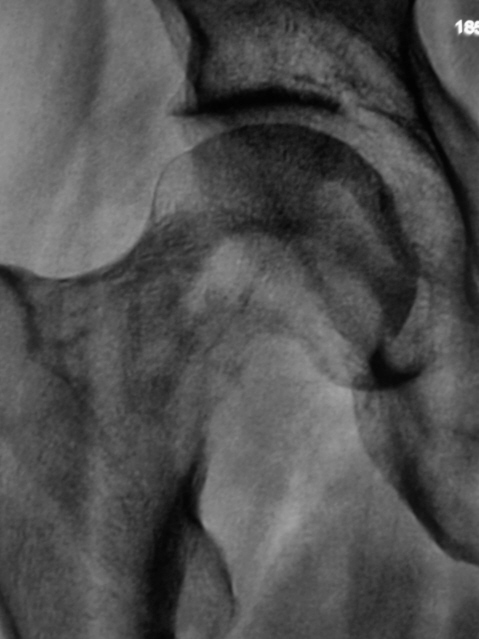

Но пациент предъявляет также жалобы на боли в области бедра и тахобедренного сустава. Произвели рентгенографию тазобедренного сустава в прямой проекции.

12..Ranee_.jpg

Метастазирование паратрахеальных л/узлов, местаз шейки бедренной кости :-(.